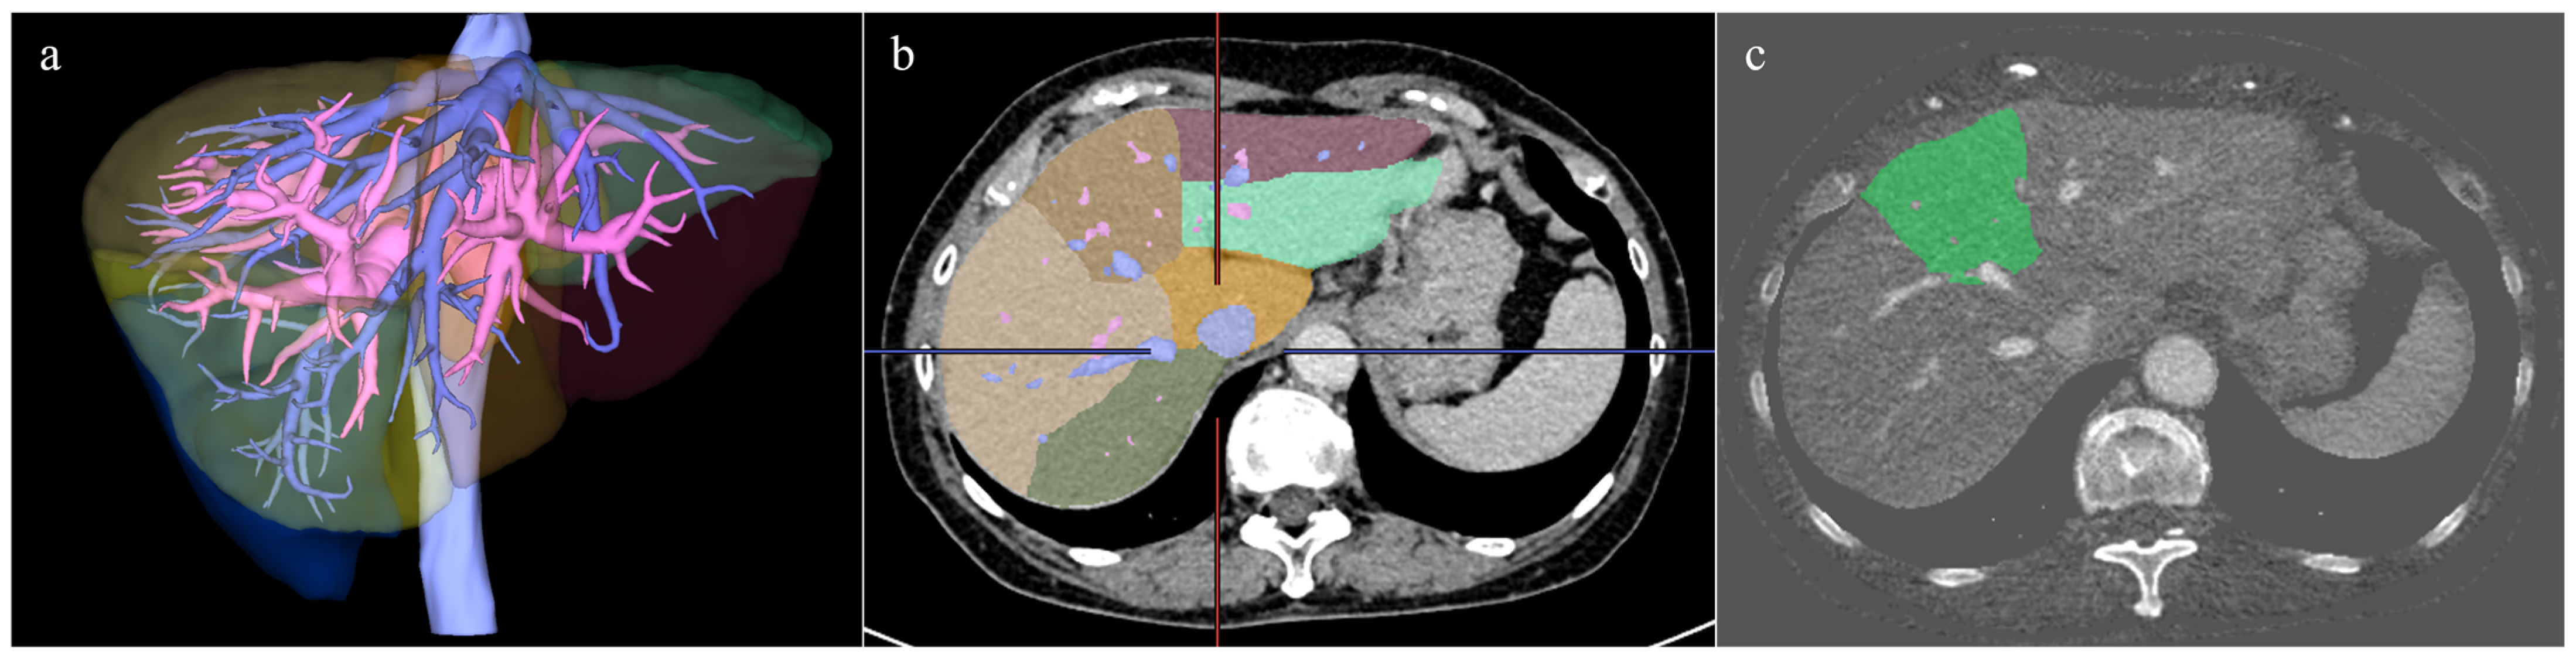

2.3. Image Analyses